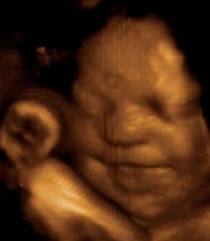

Bugün sizleri fetusların  üç boyutlu ultrason resimleri ile başbaşa bırakıyorum,harikalar!

gülücük

esneyen

uykucu

düşünceli